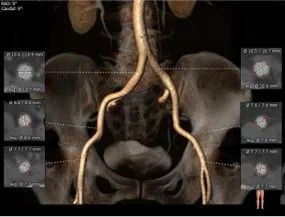

术前CT评估:

主动脉根部总览

外周血管总览

主动脉根部测量:

三叶式主动脉瓣,L-N间纤维融合,无钙化,小瓦氏窦,非横位心。

冠脉测量:

冠脉开口高度可,左、右窦未见冗长瓣叶

主动脉弓测量:

主动脉弓部宽度、角度可

外周血管入路:

外周血管内径可,走行适宜,穿刺点无钙化